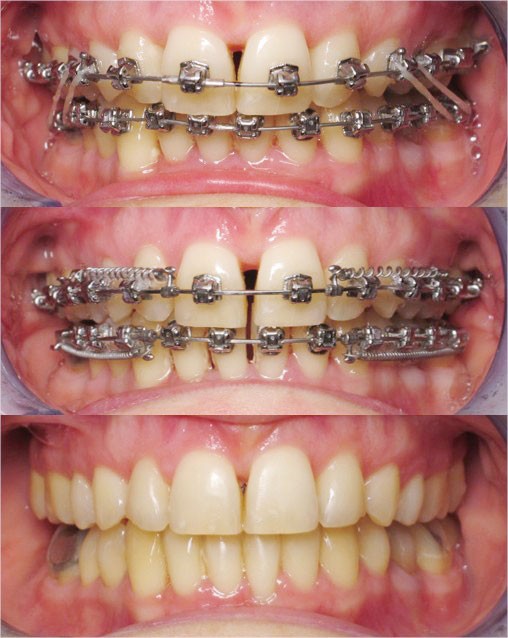

Conclusion

Les objectifs de traitement ont été remplis. Nous avons observé un excellent contrôle du torque et une absence de perte de l’occlusion postérieure grâce à la technique Insignia.